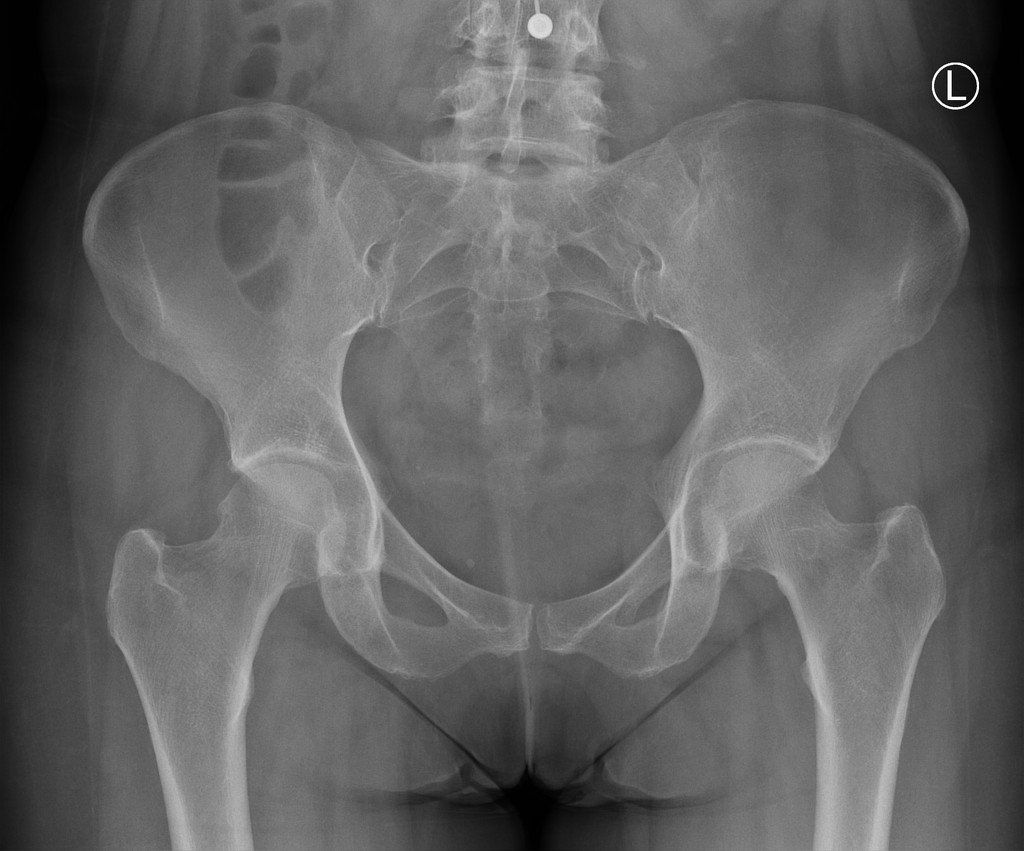

The anatomy of the hip can be complex and it is important that a thorough objective assessment follows the subjective history taking. You will be asked to perform your provocative movements and activities as well as active and passively assessing the range of movement of your hip. This is important as other conditions which could mimic adductor related groin pain could be cam and pincer syndrome, inguinal hernia, iliopsoas bursitirs, neural compress, snapping hip syndrome or pain orginating from a visceral structure.